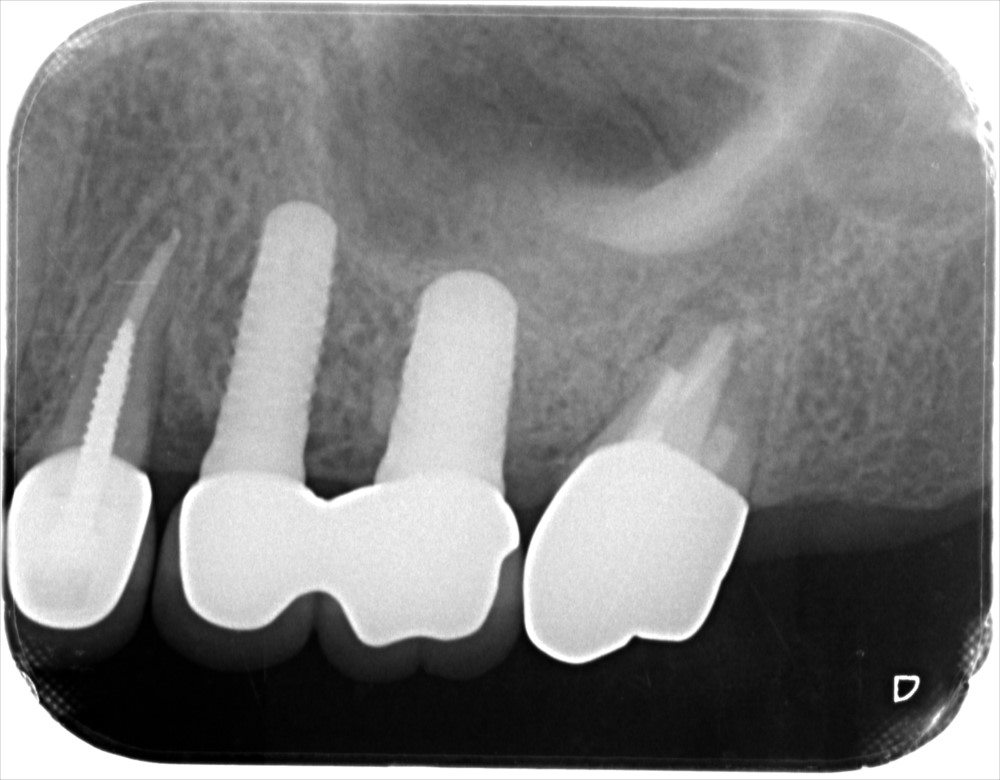

治療後のレントゲン写真です。治療しても、歯茎の腫れは治まらなかったので、取りきれない汚れがあると判断し、意図的歯牙再植術を行いました。

術直後のレントゲン写真です。

術後1年後のレントゲン写真です。根の先の炎症が小さくなっているのがわかります。歯茎の腫れもなく経過は順調です。